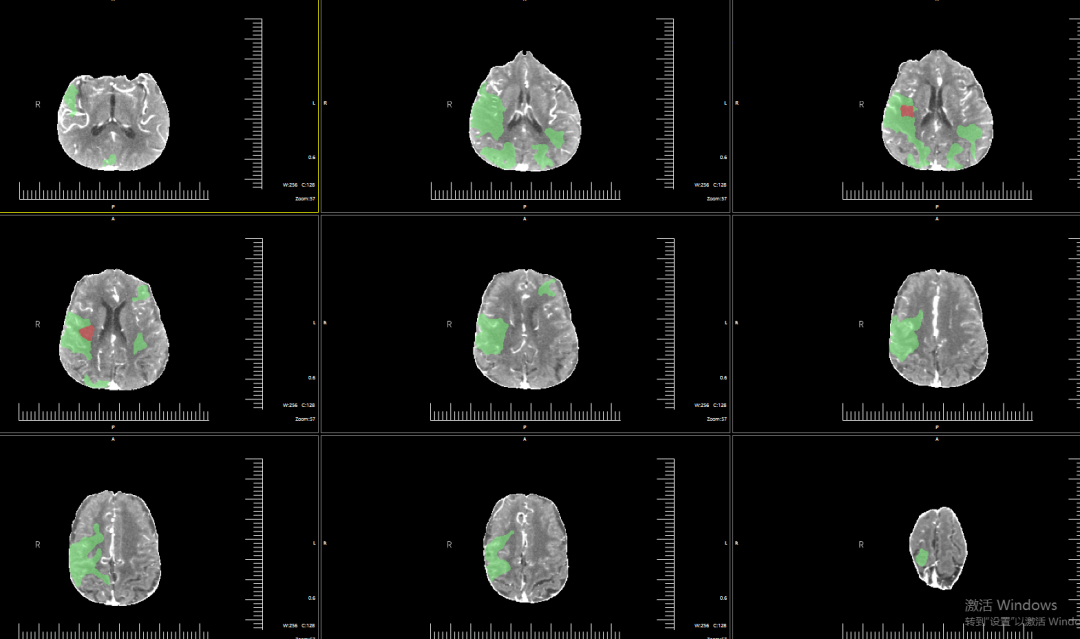

CTP提示核心梗死体积2.4ml,Mismatch体积160.8ml,低灌注区体积163.2ml,Mismatch比值为68。

动脉长鞘怎么置入有励可说|Locaste 088励楷长鞘及Tarvos微导丝在右侧大脑中动脉M2段取栓术中的应用_https://www.jmylbn.com_新闻资讯_第9张

术后影像

术后即刻影像。

术后复查CT、TCD。